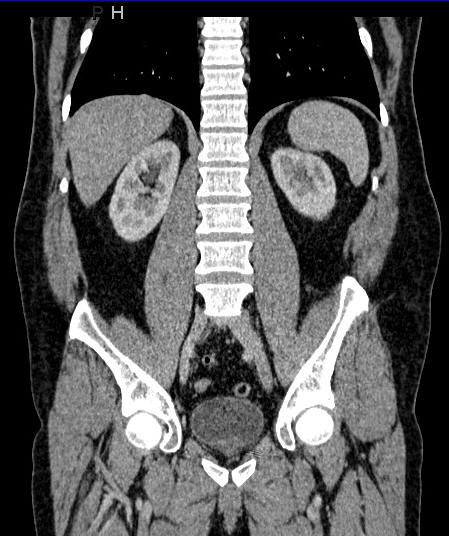

An abdominal CT scan offers images of the internal organs,

bones, soft tissue and blood vessels of the belly area. This procedure is

typically used to help diagnose the cause of abdominal or pelvic pain and

diseases of the internal organs, small bowels and colon. It is also

performed to guide biopsies and drain abscesses, plan for and assess the results

of surgery and stage, plan and properly administer radiation treatments for

tumours.